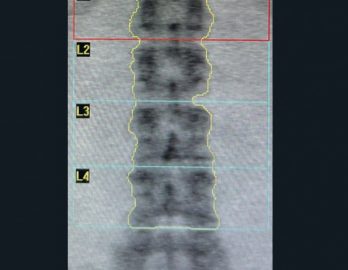

Especialista en diagnóstico por imágenes con más de 25 años de experiencia en el campo del ultrasonido y radiología digital. Trabajamos con equipos de alta tecnología garantizando la calidad y seguridad de nuestros diagnósticos, pues nuestra prioridad es la salud, bienestar y satisfacción de nuestros pacientes.

Sabemos que visitar un centro médico a veces genera nervios. Por eso, hemos creado un ambiente cálido, moderno y 100% seguro para ti. Desde nuestra cómoda sala de espera hasta nuestras áreas de ecografía, mamografía y rayos X, cada rincón está equipado con tecnología de última generación y diseñado para que te sientas en confianza.